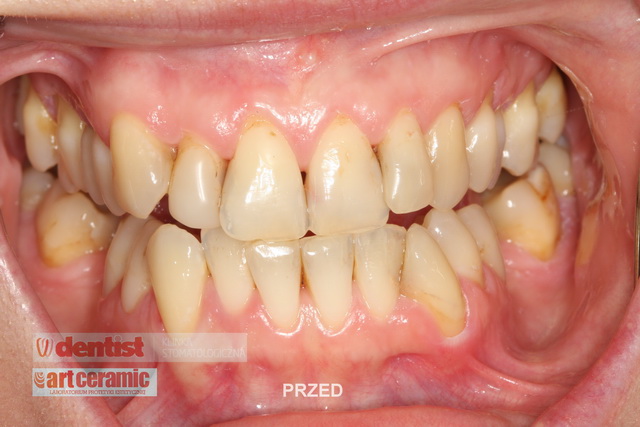

Przedstawiamy przykładowe prace oraz ich efekt po zacementowaniu w ustach pacjentów.

Wysoka estetyka oraz wierne odwzorowanie natury są naszym priorytetowym celem.